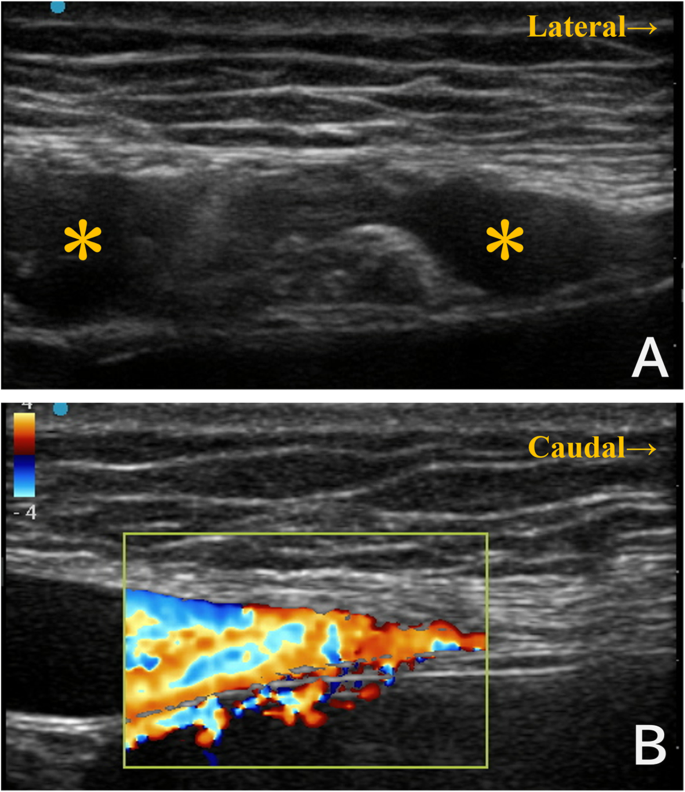

然而,在进行超声引导下的直肌鞘阻滞过程中,发现左侧腹直肌内存在扩张的血管结构(见图1A)。彩色多普勒超声证实了这些结构的血流存在,表明它们是扩张的静脉(见图1B)。因此我们中止了直肌鞘阻滞,转而实施了横向腹横肌平面阻滞。术后对术前CT片的复查显示,腹部壁的静脉在腹直肌内也有扩张(见图2)。

图1

尝试进行直肌鞘阻滞时的超声所见。(A) 轴向超声图像显示左侧腹直肌内的血管结构。(B) 矢状多普勒超声确认了血管的血流